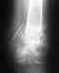

Re: чрезвертельный перелом правого бедра со смещением

послал Alexander Chelnokov 10 Июль 2013, 00:21

Операция нужна, чем раньше - тем лучше. Пока пациентке надо начать вводить антикоагулянты (клексан, фраксипарин). Можно сделать у нас. Звоните 371-31-82 или заедьте к нам на Московскую, 12 за вызовом на госпитализацию.